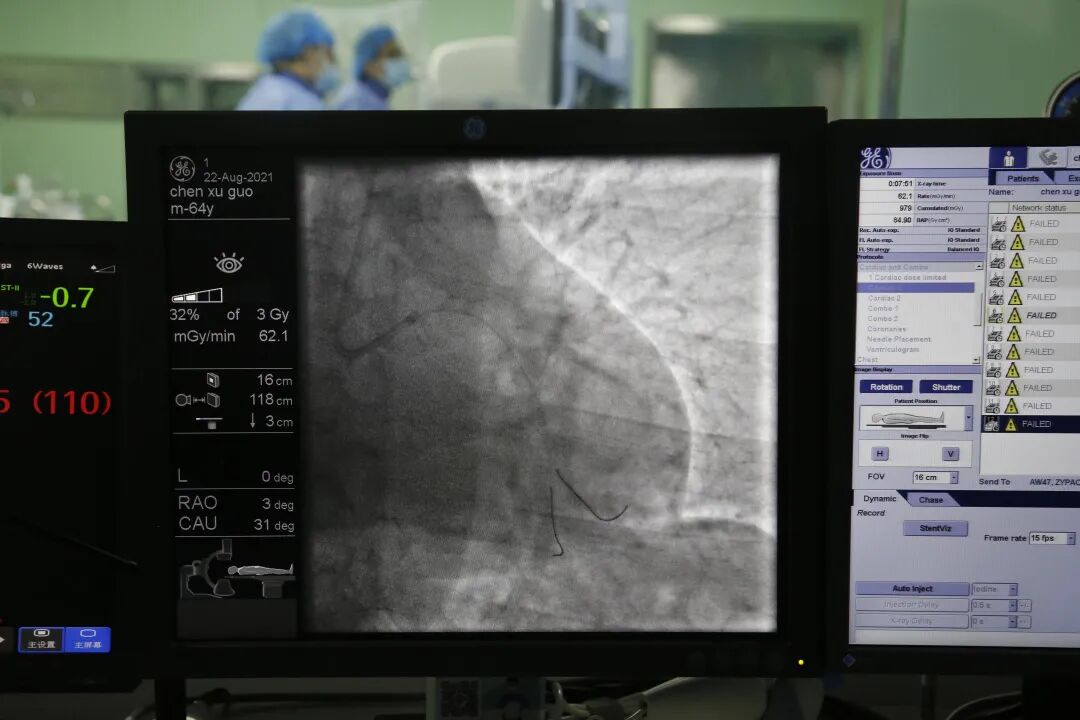

8月22日上午,在山东第一医科大学第一附属医院(山东省千佛山医院)心内科赵学强教授的指导下,在新泰市中医医院影像科董晓副主任、导管介入室李树娟副护士长等医护人员配合下,心血管病科房立文副主任、季仁波主治医师对局部浸润麻醉的上述患者实施DSA冠脉造影,结果显示:冠脉走行区均可见钙化影,左主干未见明显狭窄,前降支近中段可见60-70%狭窄,管壁钙化,TIMI血流3级。回旋支中段75%狭窄,TIMI血流3级,钝缘支开口90%狭窄,TIMI血流3级,管壁钙化。回旋支远段60%狭窄,TIMI血流3级。右冠近中段弥漫性钙化病变,狭窄50-60%,TIMI血流3级。

经与患者家属沟通,决定对病变明显的回旋支行PCI术,对其他病变血管暂时行内科药物保守治疗。术中应用导丝分别送至回旋支远端及钝缘支远端,应用球囊预扩张后造影显示病变血管狭窄改善不明显,遂给予支架一枚释放于回旋支中段至钝缘支开口,血管狭窄得到显著改善,手术顺利,病人术中无不适,拔除鞘管局部加压包扎,患者安返病房。